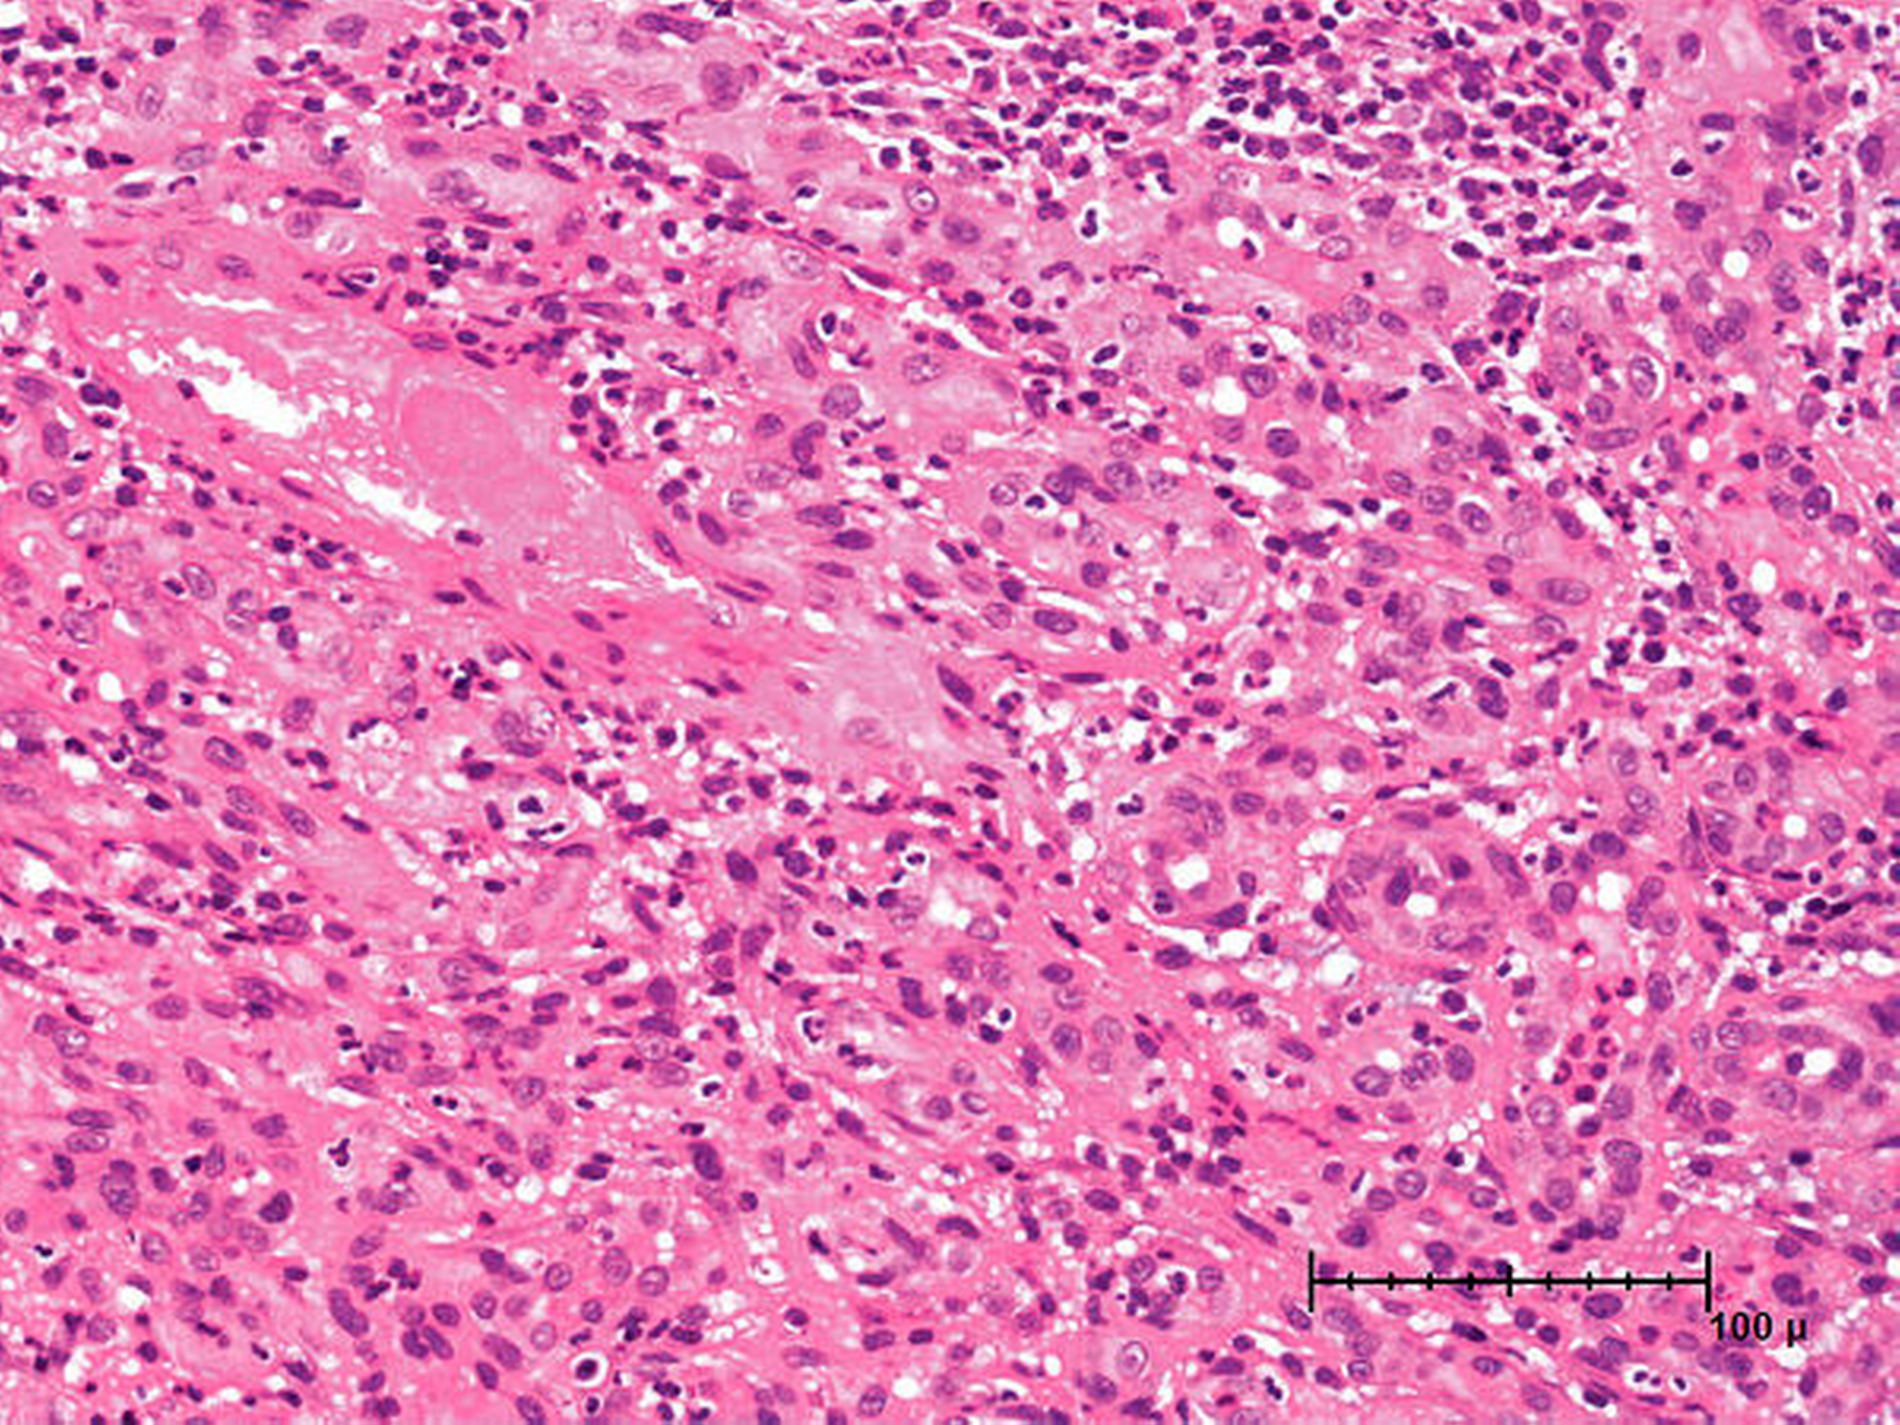

In der histologischen Untersuchung zeigte sich in der Übersichtsvergrößerung ein ulzerierter, etwas polypöser Hauttumor, der aus verzweigten, teilweise dickwandigen Kapillaren mit dichter entzündlicher Begleitinfiltration bestand (Abbildung 5). In der Detailaufnahme bei höherer Auflösung sind die zahllosen Kapillaren im umgebenden zellreichen Stroma mit Entzündungsinfiltraten gut erkennbar (Abbildung 6). Es fanden sich keine zellulären Atypien.